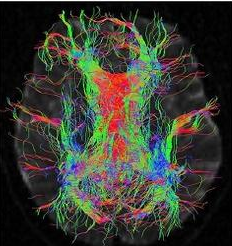

研究の結果、エ〇チな動画をたくさん見た人は脳の刺激中枢部分が委縮した脳をしています。

研究者たちは「エ〇チな動画をたくさん見た人の場合、脳の領域の中で刺激と報酬反応を司る線条体が委縮していることが確認できた」という衝撃的な結果を伝えました。